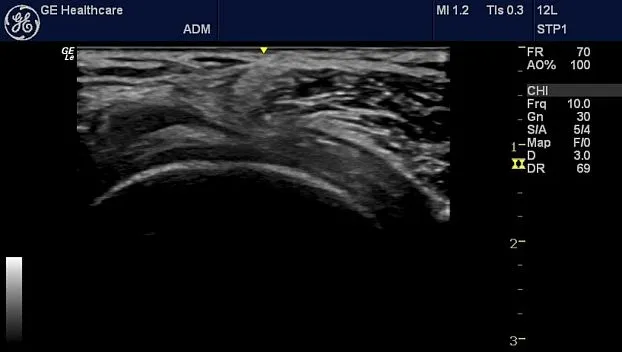

Клинические изображения

- 12L-RS, линейный датчик, широкополосный, мультичастотный с диапазоном частот 4,2-13,0 МГц. Клиническое применение: периферические сосуды, поверхностно расположенные органы и структуры, скелетно-мышечные, нервные блокады, плевра, офтальмология и контроль иглы

- L4-12t-RS Линейный датчик, широкополосный, мультичастотный с диапазоном частот 4,2-13,0 МГц и с 4 программируемыми кнопками. Клиническое применение: периферические сосуды, поверхностно расположенные органы и структуры, скелетно-мышечные, нервные блокады, плевра, офтальмология и контроль иглы